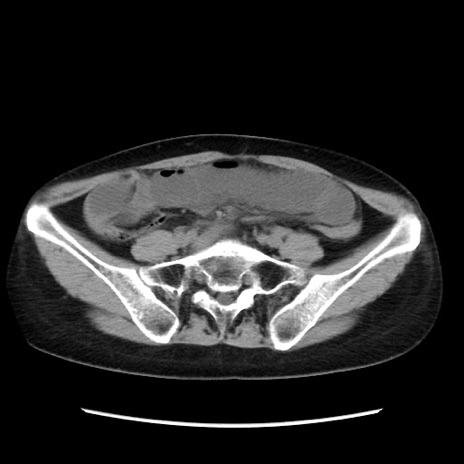

症例32(横断像)

【症例】40歳代 女性

【主訴】上腹部痛、嘔気・嘔吐

【現病歴】約9時間前頃から急に上腹部痛、嘔気、嘔吐が出現。改善しないため救急要請。

【既往歴】子宮頚癌(広汎子宮全摘術、放射線療法)、腸閉塞

【身体所見】腹部:平坦、軟、腸雑音亢進、上腹部を中心に腹部全体に圧痛あり。

【データ】WBC 8400、CRP 0.03